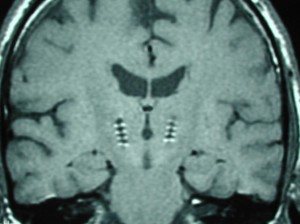

Schéma uloženia mozgového stimulátora (hore) a magnetická rezonancia mozgu so zavedenými milimetrovými elektródami (dole). Efekt hlbokej mozgovej stimulácie umožňuje znížiť množstvo podávaných liekov, prípadne niektoré lieky celkom vysadiť. Predíde sa tak rozvoju príznakov spôsobených dlhodobou štandardnou liečbou (levodopa).